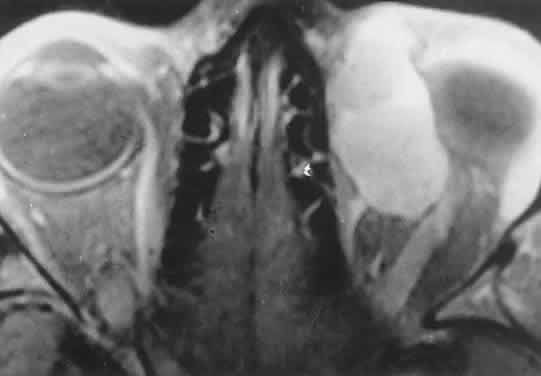

Fig. 2. MRI shows an intraconal tumor of lower intensity than the medial rectus muscle. The proximal muscle is splayed rather than compressed, suggesting that the lesion originated within the medial rectus. The diagnosis was alveolar rhabdomyosarcoma.

Within the orbit, rhabdomyosarcoma occurs most often, but not exclusively, in the superior nasal quadrant, with downward and outward displacement of the globe. CT scans show the topography of the orbital mass (Fig. 1A), as well as the possible extension into adjacent bone, paranasal sinuses, or the intracranial cavity. The circumscription that may be noted on CT is relative, because the lesion is not encapsulated and microscopically infiltrates normal tissue. Echography shows internal echoes of low-to-medium amplitude. Because the cellular tumor absorbs acoustic energy, the amplitude of the spikes falls off somewhat through the lesion (see Fig. 1B and C). MRI can help define the tumor's relationship to extraocular muscles (Fig. 2).